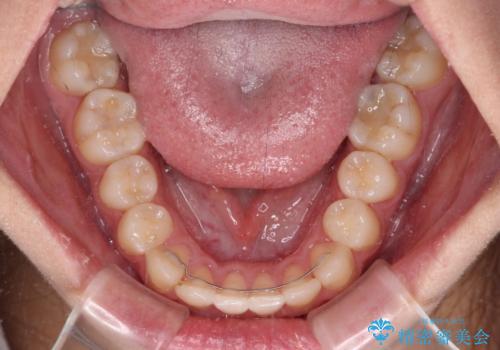

前歯のクロスバイトを短期間で解消 目立たないワイヤー矯正

- 1年1ヶ月

- 矯正治療後の保定が不十分だと後戻り(元の位置に戻ろうとする動き)をします